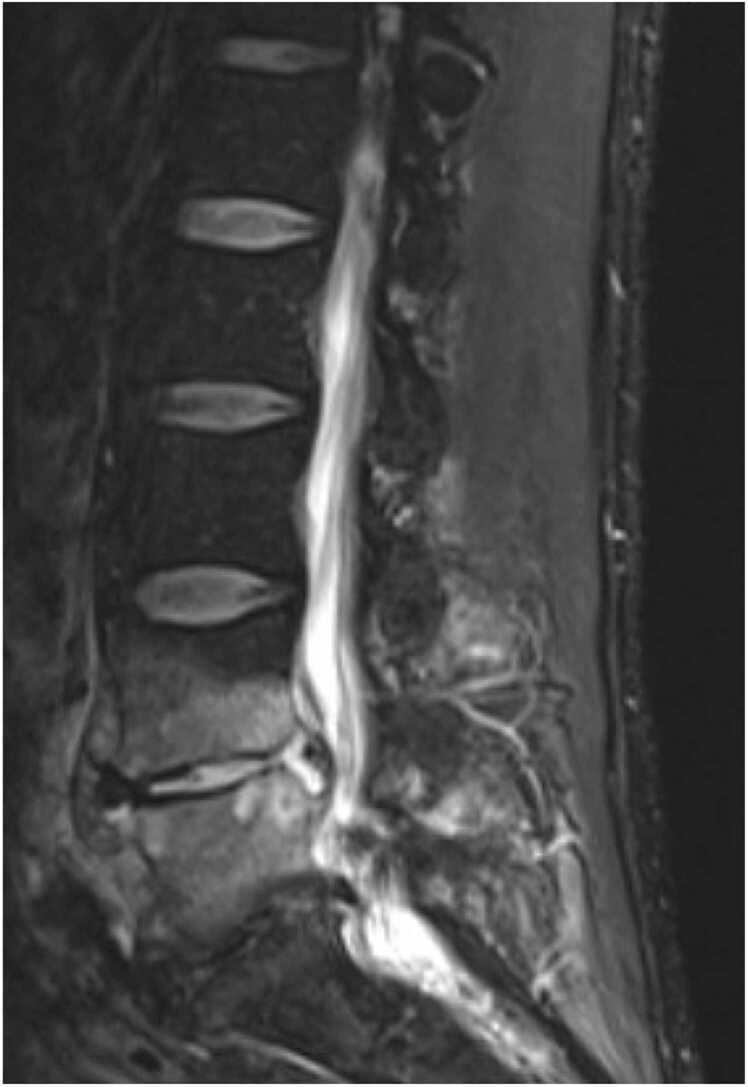

A 55-year-old-male with a chronic left uretero-pelvic junction (UPJ) obstruction managed with intermittent stent exchanges presented with low midline back pain. CT Abdomen/Pelvis revealed spondylodiscitis at L4-L5, further demonstrated on MRI Lumbar spine. Imaging also revealed the left nephro-ureteral stent was mispositioned, with some mild wall thickening of the left ureter. He was not systemically ill, and antimicrobials were held. He underwent a L4/5 disc biopsy, and pathology revealed acute discitis. Blood and biopsy cultures remained negative through hospital day 5. He then underwent repeat L4/5 disc biopsy. Cultures of repeat biopsy resulted in Gardnerella vaginalis. IV antimicrobials were stopped, and oral Metronidazole was started. He completed 10 weeks of Metronidazole therapy, with significant clinical improvement.

Abstract Image